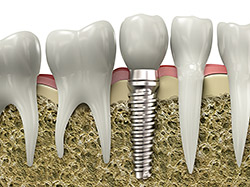

An implant is a synthetic tooth root in the shape of a post that is surgically placed into the jawbone. The “root” is usually made of titanium (the same material used in many replacement hips and knees), a metal that is well suited to pairing with human bone. A replacement tooth is then fixed to the post. The tooth can be either permanently attached or removable. Permanent teeth are more stable and feel more like natural teeth.

The ideal candidate for implants is a non-smoker who has good oral health, including a sufficient amount of bone in the jaw and healthy gums with no sign of gum disease.